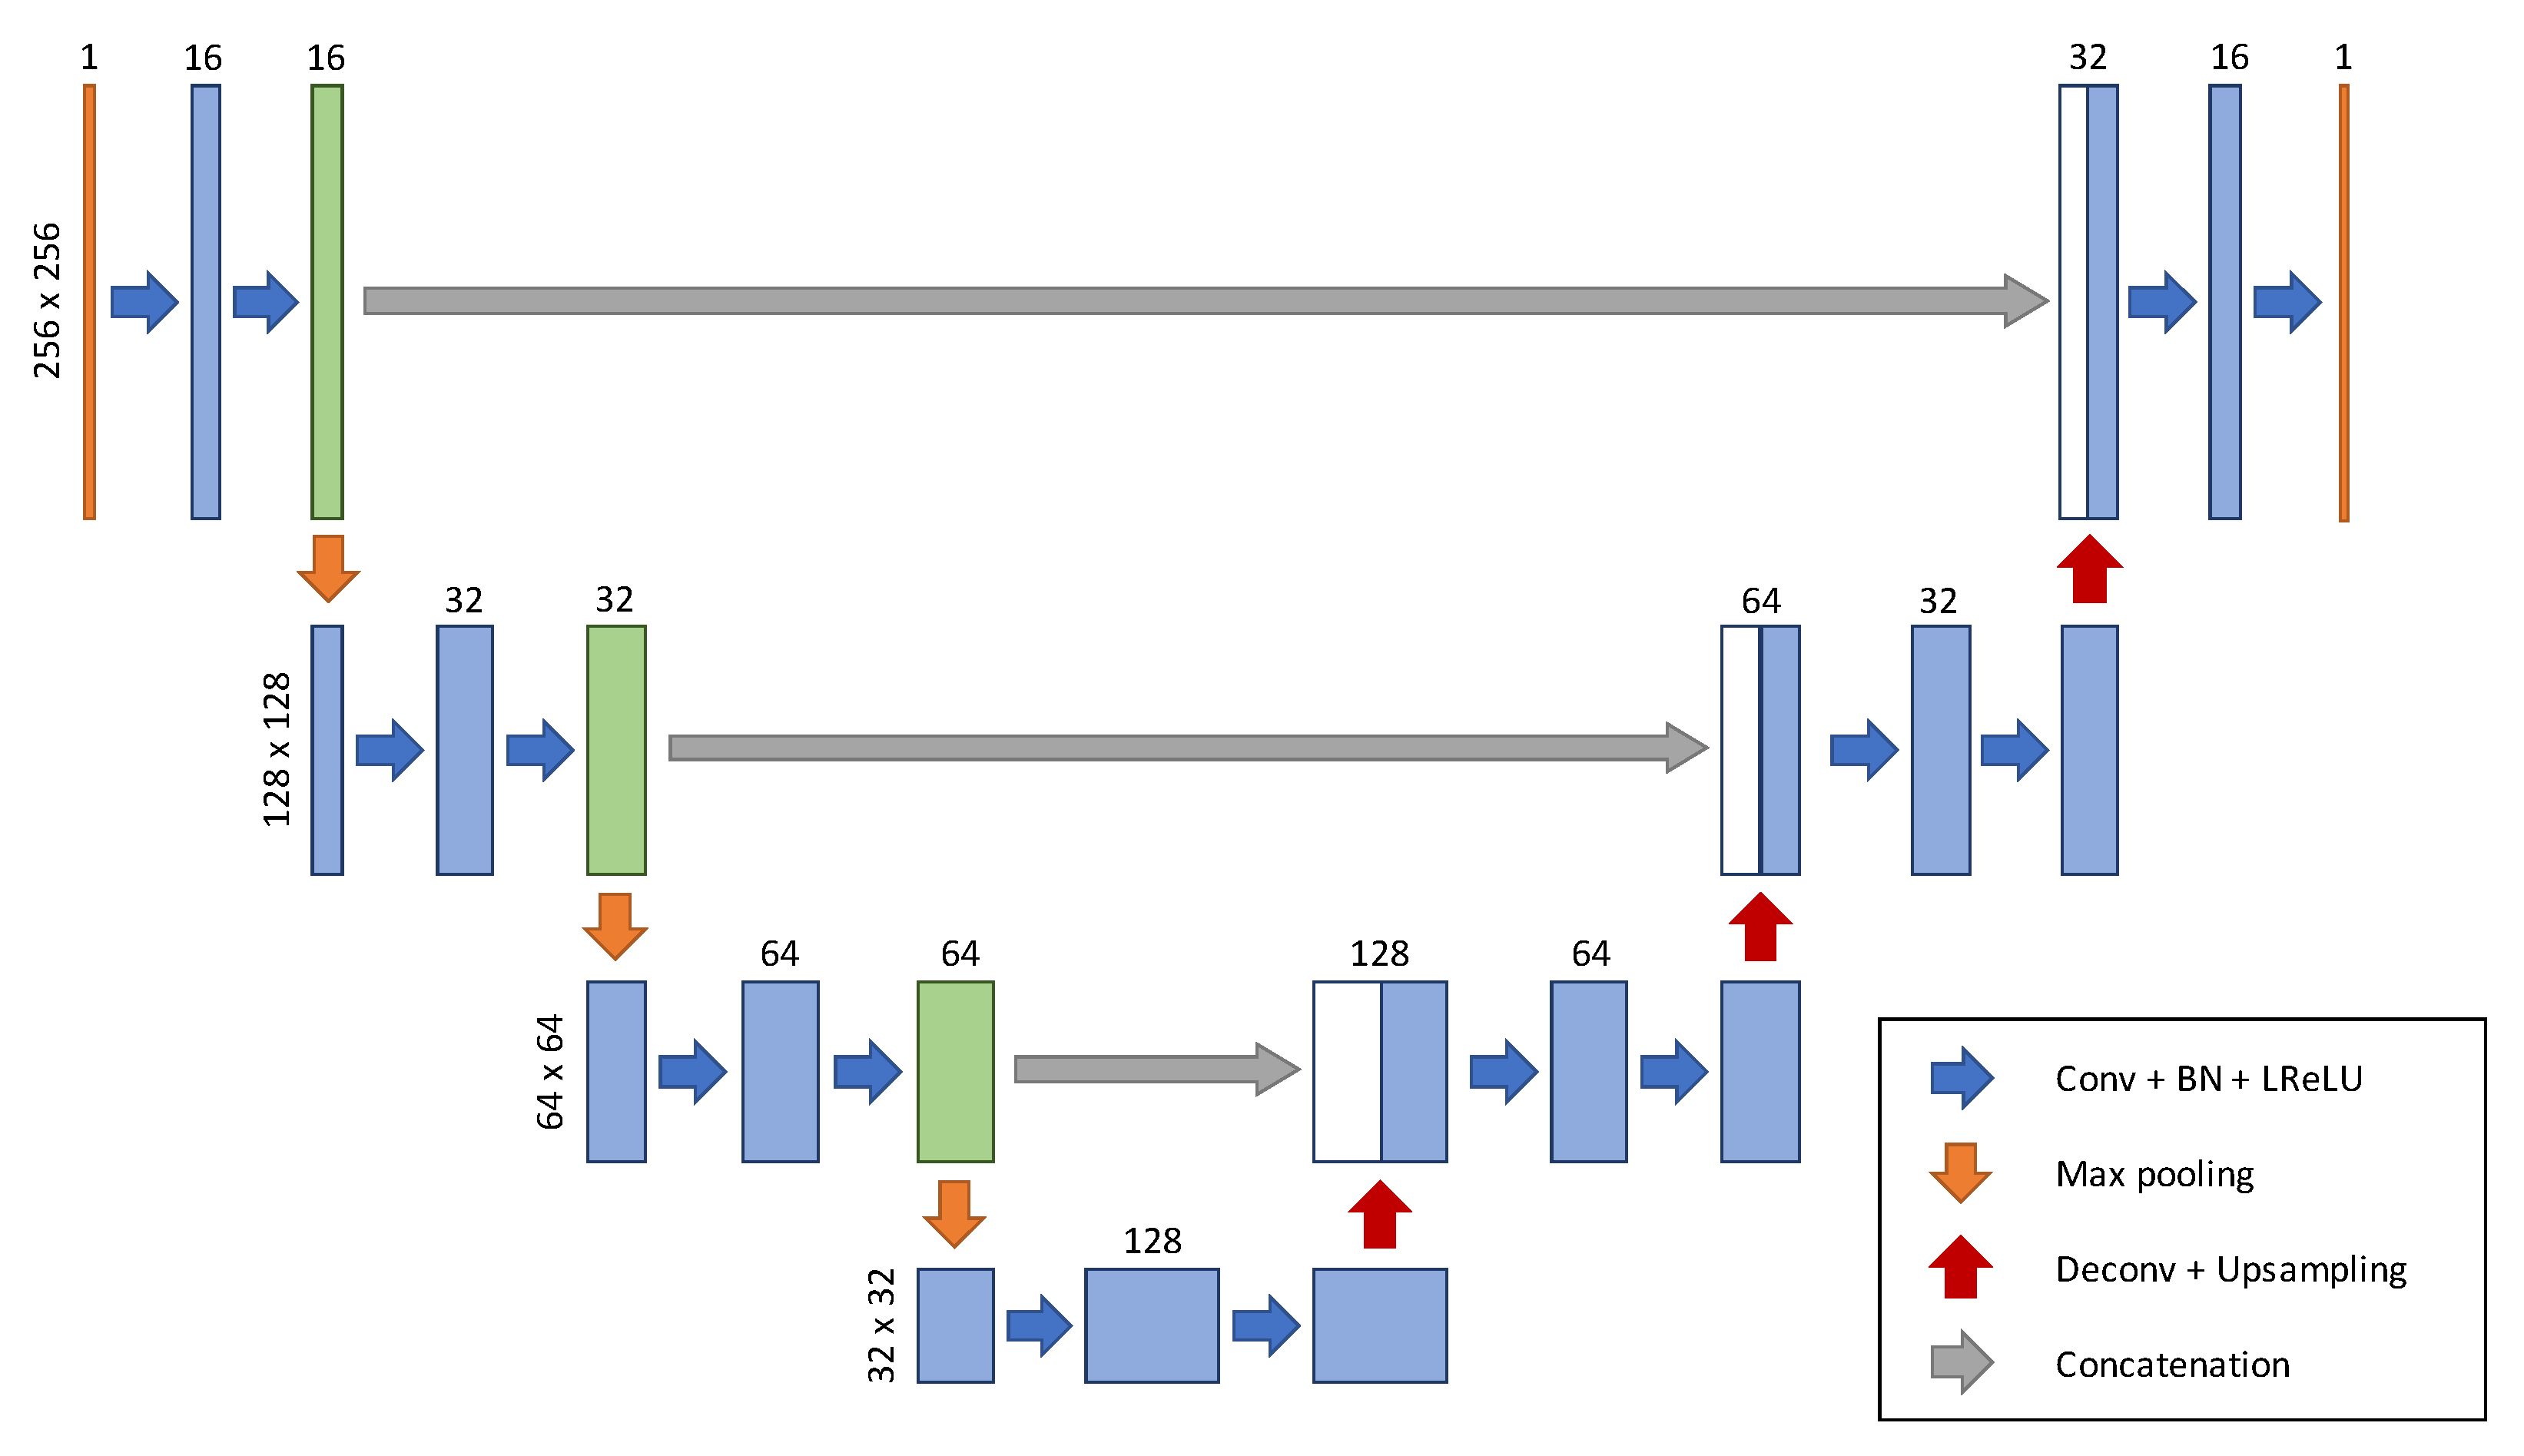

2.2. Network Architecture